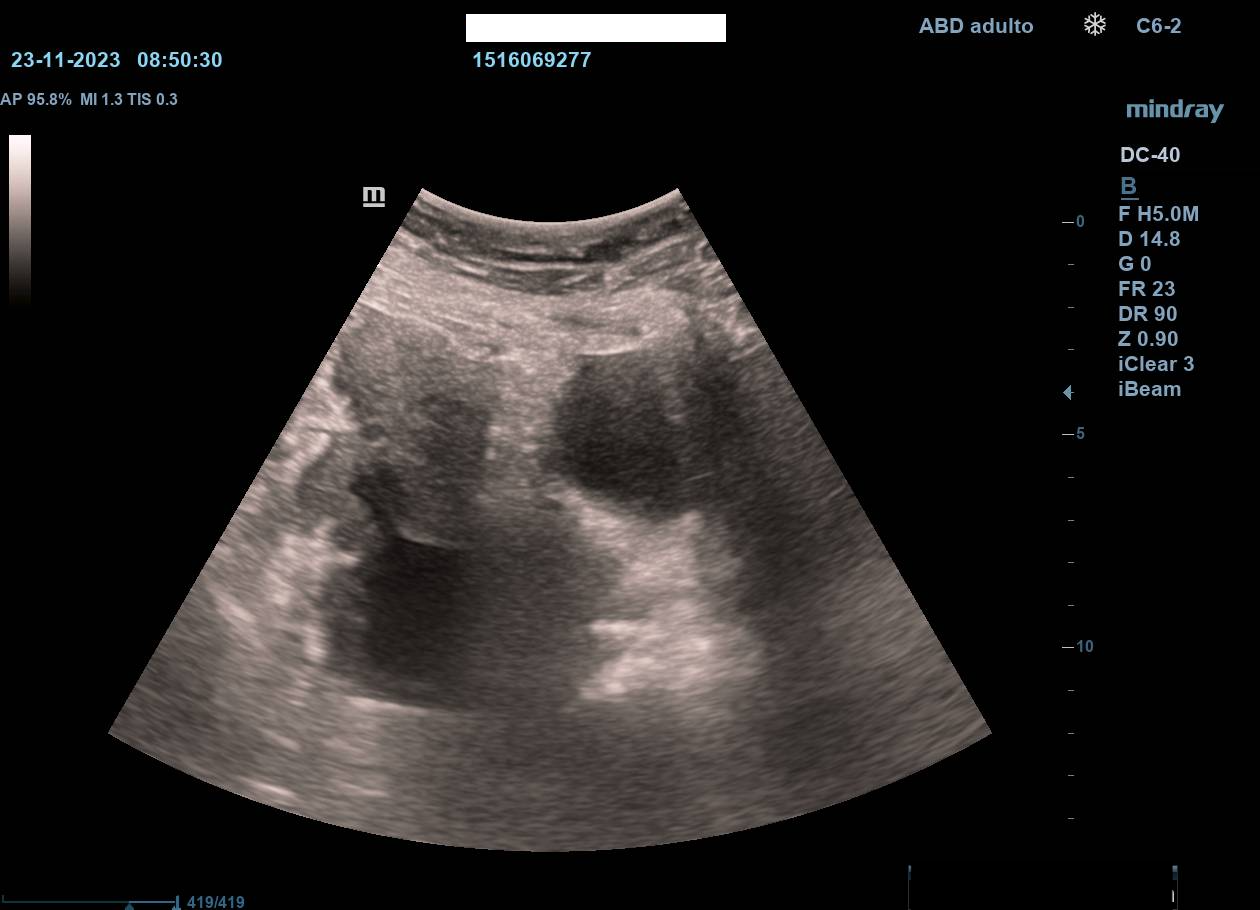

Hallazgos ecográficos

La ecografía en atención primaria permitió un abordaje inicial inmediato, objetivándose dilatación de asas intestinales en la zona de la tumoración, sospecha de ascitis y no visualización de riñón izquierdo (atrofia previa). Estos hallazgos, junto con la exploración, motivaron derivación urgente a Medicina Interna con sospecha de tumoración abdominal.